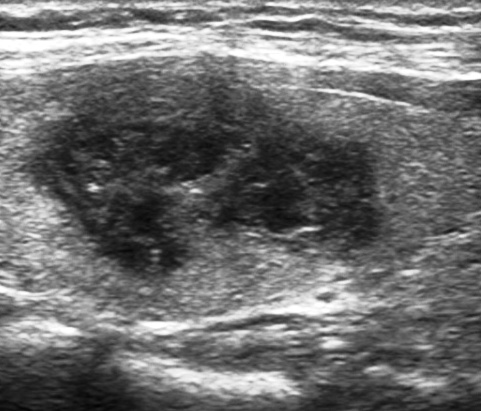

Case 2 : Thyroid Malignancy

A 27 year female complained of swelling in left side neck and it notably increased over a period of 6 months.

Ultrasound Images:

Ultrasound features of a malignant thyroid nodule : solid, hypoechoic irregular margins, absence of a hypoechoic halo around the nodule.

Hypoechoic lesions have a higher risk of being malignant. Lymphadenopathy and local invasion of adjacent structures are highly specific features of thyroid malignancy but are less commonly seen.